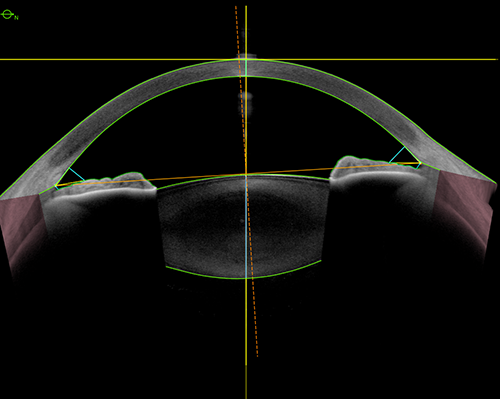

Adding to the powerful Metrics App, ANTERION can now automatically detect the scleral spur, an important anatomical landmark in the anterior chamber. This allows for the automatic calculation and visualization of many biometric parameters. Clinicians can benefit from improved workflows and precise anterior chamber parameters.

ANTERION metrics that are generated based on the location of the scleral spur